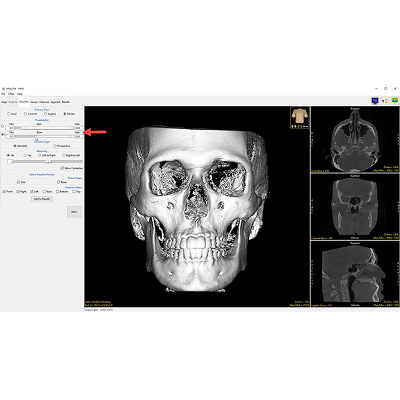

The HNA app opens to the first function tab, which is the Align tab. This provides a way to realign the volume if it wasn’t lined up precisely as desired during the scan procedure.

The Visualize tab in the HNA module is designed to provide an assessment of the previous alignment step and to explore and record various visualizations or views of the subject.